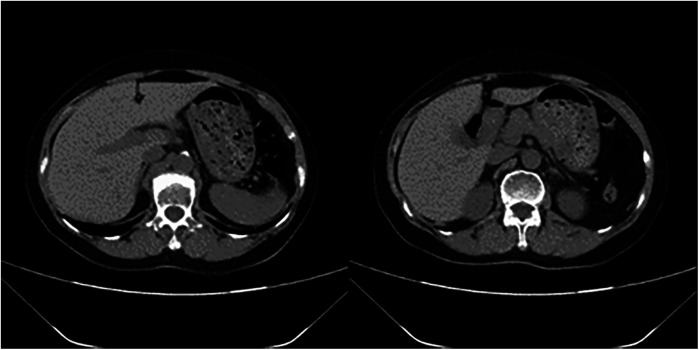

Postoperative pulmonary embolism (PE) poses a serious threat to a patient's life. However, cases involving concurrent liver rupture are exceedingly rare. This report describes a case of a patient who experienced cardiac arrest due to PE following lower extremity varicose vein surgery, followed by liver rupture during cardiopulmonary resuscitation (CPR). Under the timely intervention of a multidisciplinary team (MDT), the patient underwent extracorporeal membrane oxygenation (ECMO)-assisted resuscitation and hepatic repair surgery. Through a staged anticoagulation strategy, a balance was achieved between bleeding control and thrombosis prevention. Ultimately, after 23 days of treatment, the patient regained consciousness and was transferred to rehabilitation.